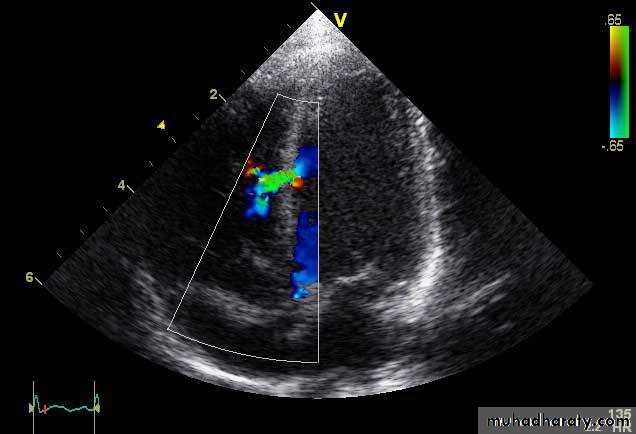

Echocardiography

Usually done after reperfusion therapy

Can be performed at the bedside

Useful to assess the status of the LV & RV

Detects mechanical complications

LV mural thrombus

Ventricular septal rutpture

Mitral regurgitation

Pericardial effusion

RV infarction

Dx: echo and Doppler

Diagnosis: echo and Doppler